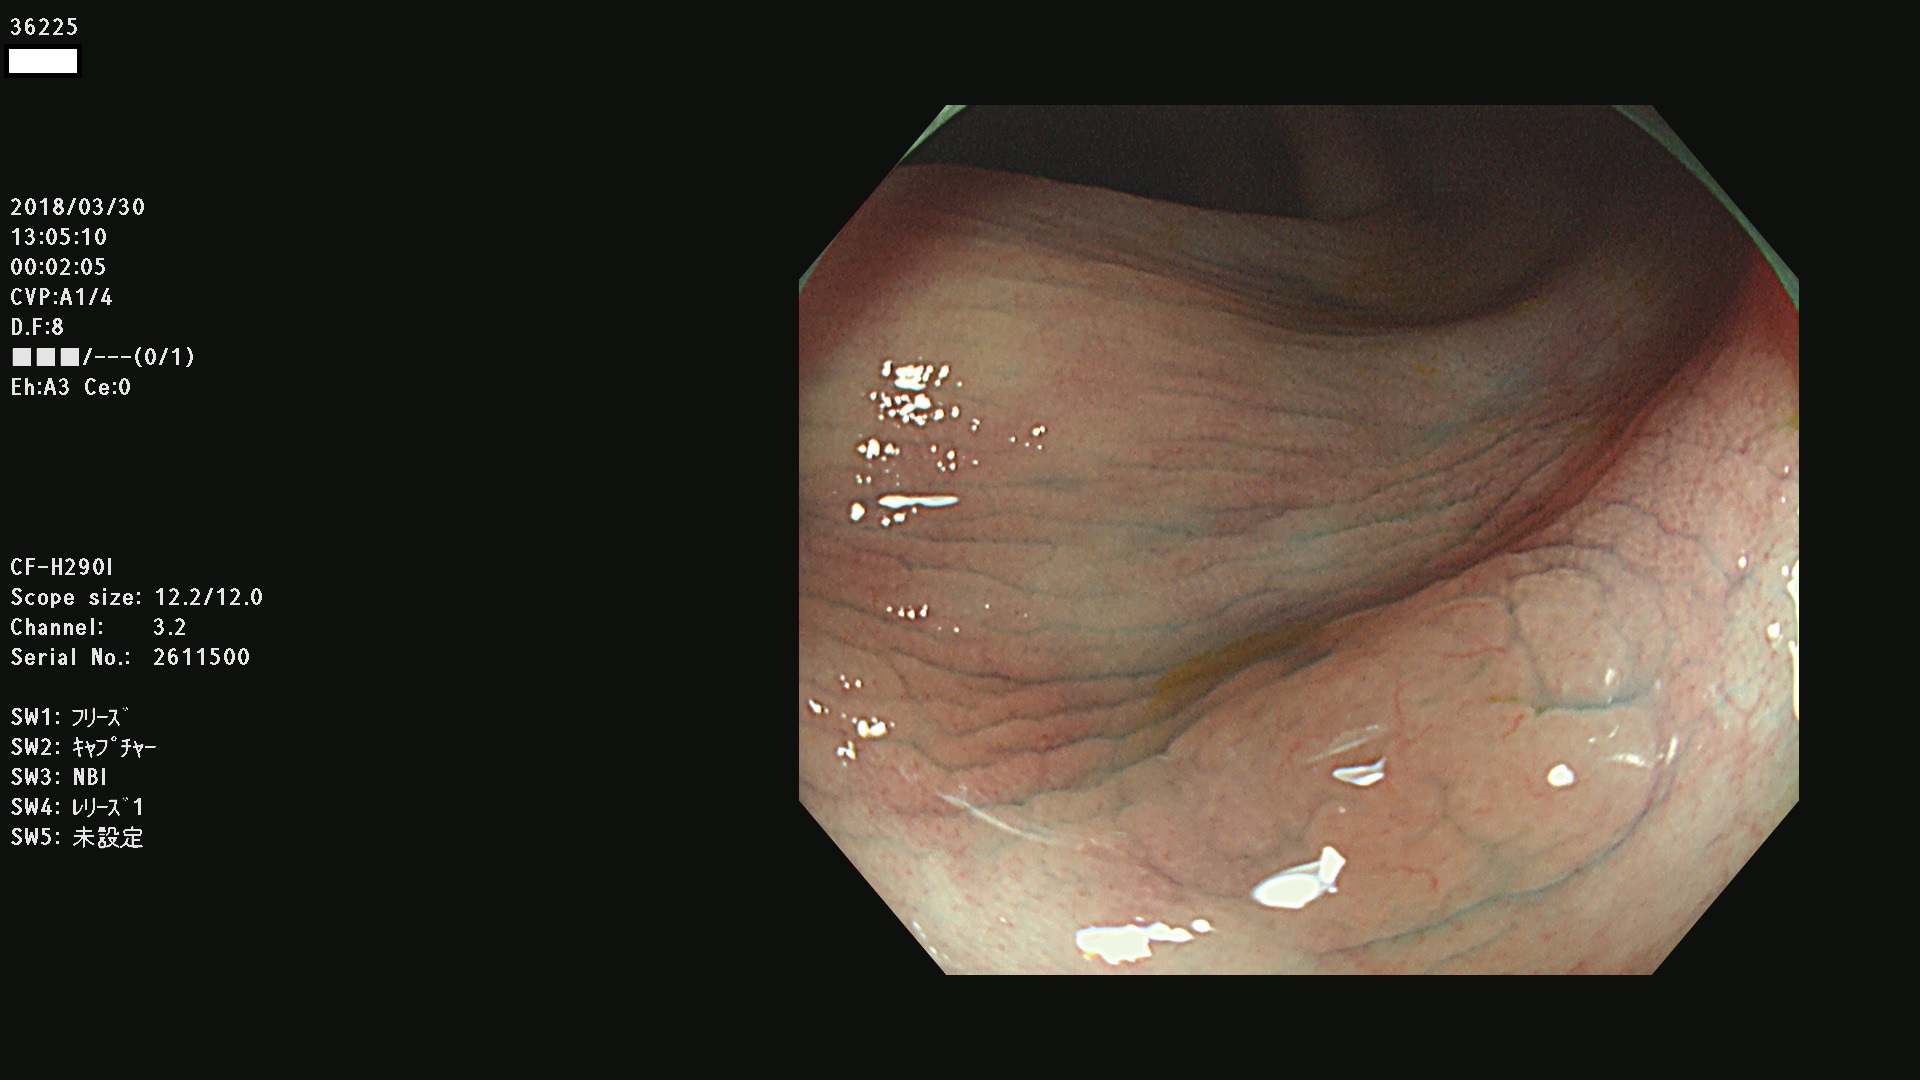

36201 36202 36203 36205 36207 36209 36210 36212 36213 36214 36215 36217 36220 36221 36222 36224 36225 36226 36227 36229 36230 36231 36232 36235 36236 36238 36240 36243 36244 36246 36247(SSAPのみ。SPS) 36248 36249 36251 36252 36253 36254 36255 36256 36257 36258 36259 36261 36262 36264 36265 36267 36269 36270 36272 36274 36275 36276 36279 36280 36281 36283 36285 36288 36289 36291 36292 36295 36296 36297 36299

発見困難で危険性の高い平坦型病変(上記100名より抽出)